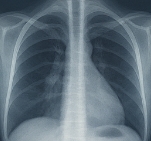

폐암 초기증상이 의심된다면 지체하지 말고 병원에서 검진을 받아야 합니다.

- 흉부 X-ray 검사: 폐 구조 확인.

- 저선량 CT 검사: 조기 폐암 진단에 효과적.

- 세포검사: 가래나 기관지 세포를 검사해 암세포 여부 확인.

폐암 초기증상 발견 시 빠른 진단이 생존율을 크게 높입니다.